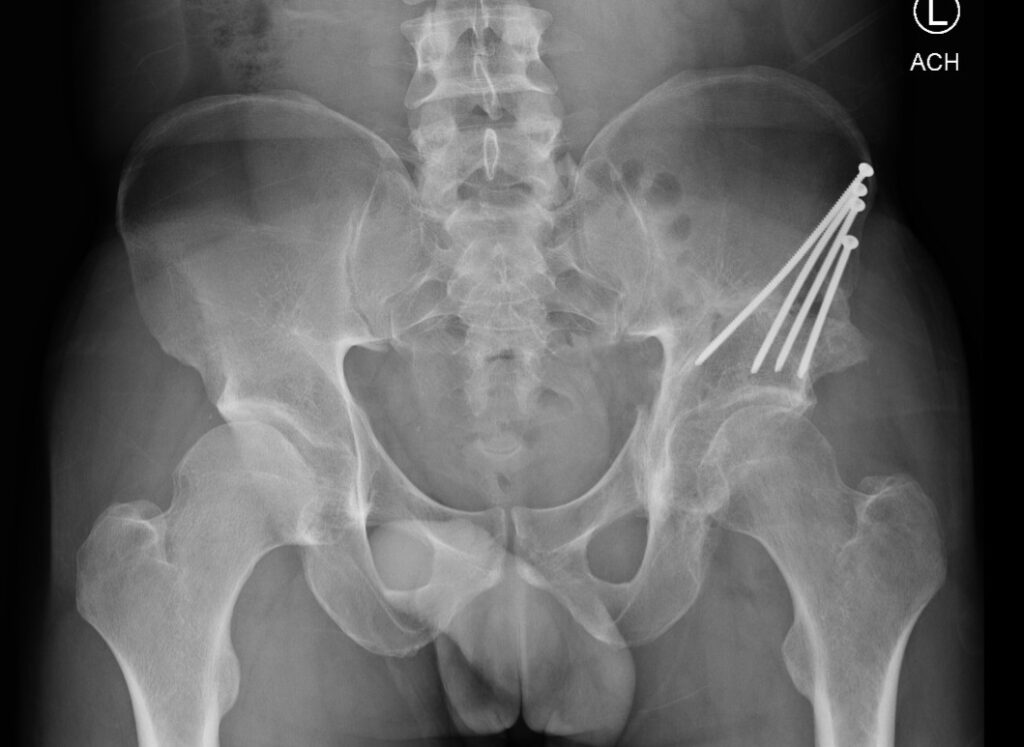

Example of Periacetabular Osteotomy

Postoperative xray of a partially healed periacetabular osteotomy